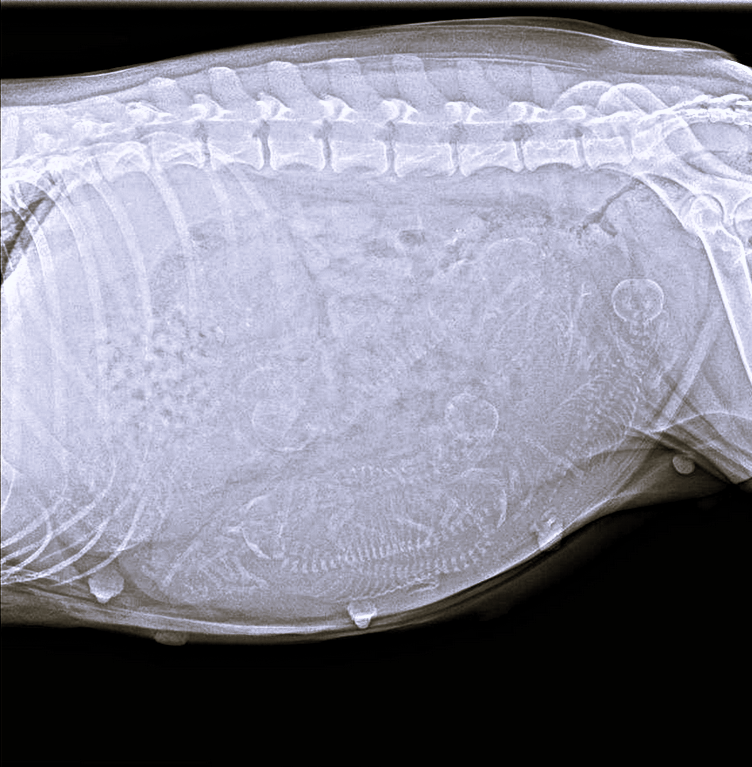

Een week voor de uitgerekende datum ‘vrijdag 29 augustus’, wordt een röntgenfoto ( RX ) gemaakt en krijgen we een beter beeld van het aantal pups dat zal verwacht worden.

De RX is ondertussen gemaakt. De dierenarts wist ons te vertellen dat er minimaal 8 pups op zitten. En net zoals bij het laatste nestje van haar ‘moeder Miyo’, zouden het er ook 9 pups kunnen zijn, dit is niet helemaal duidelijk op de foto te zien.

Op een röntgenfoto zijn de botten van de pups goed te zien, waardoor het aantal ‘skeletjes’ kan worden geteld.

Door de röntgenfoto te maken één week voor de worp, kan de dierenarts een goede schatting maken van het aantal pups.